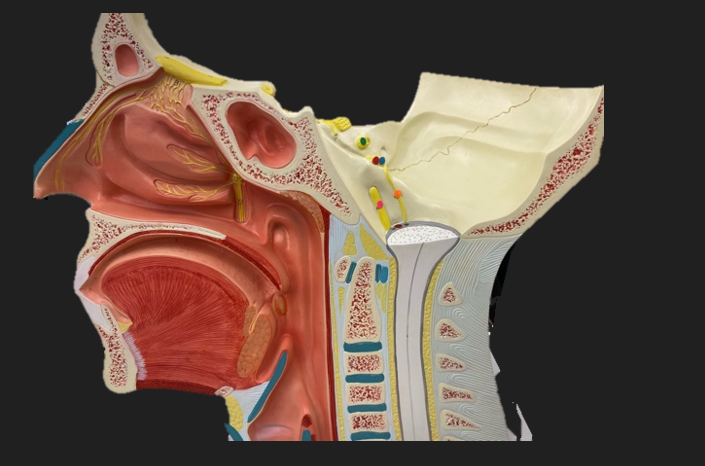

olfactory tract

red dot

corpora quadrigemina

dark green dot

cerebral aqueduct

blue dot

cerebral penduncles

pink dot

pons

orange dot

medulla oblongata

yellow dot

mammillary body

red dot

corpus callosum

dark green dot

pineal gland

yellow dot

epithalamus

blue dot

thalamus

orange dot

optic chiasm

pink dot

infundibulum

purple dot

cingulate gyrus

yellow dot

pituitary gland

dark green dot

pyramids

red dot

olives

blue dot

optic tract

purple dot

midbrain

green dot

folia

orange dot

arbor vitae

yellow dot

fourth ventricle

red dot

vermis

blue dot

hypothalamus

pink dot

cerebral hemispheres

yellow dot

lateral sulcus

red dot

lateral ventricles

blue dot

hippocampal gyrus